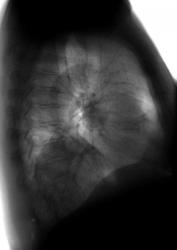

Пациентка предъявляет жалобы только на прогрессирующую потерю зрения.... Выявлена при профилактическом исследовании - окончательного мнения нет, наблюдается в динамике....

периферическая опухоль н/доли левого легкого. Учитывая жалобы, сделайте КТ (МРТ) головного мозга для исключения мтс

На мой взгляд, на настоящее время, имеет место только ателектаз нижней доли и некоторое увеличение язычкового сегмента в объёме.

На всех боковых рентгенограммах виден плавный переход контуров нисходящей аорты в "загадочное" образование - это случайное скиалогическое явление или все - таки аневризма? А образование пульсирует?

А почему на прямой рентгенограмме не виден плавный переход контуров нисходящей аорты в образование, и основная масса образования далековато о аорты7

Валентин Львович, когда периферический узел уже подрастает к корню, т.н. "централизация", нарушается бронхиальная проходимость и может развиваться гиповентиляция и ателектаз. А увеличение объема Вы наверное имели в виду в язычковых сегментах?

Нижняя доля спадается – нет сомнений. Но крупная опухоль периферического бронха должна быть видна отчётливей. И хотелось бы увидеть изображение крупных бронхов, полученное тем или иным способом.

Я так полагаю, ателектаз нижней доли. Делайте ТМГ и отправляете в онколдиспансер. Тут вероятнее центральный рак нижнедолевого бронха

Сегодня, после 8 месяцев, пришла ко мне вышеописанная пациентка. Я был удивлен и очень рад! Была она у родственников (детей) в Питере. Сделали ей операцию. Немного похудела, но чувствует хорошо. Резудьтат гистологии - лейомиома! А наши онкологи - не решились. Вот такой финал!

Лейомиома легких - редкий (за время работы - 2-3 случая встречались) случай. Заключение гистологии НИИ онкологии им. Петрова Н.Н.: Веретеноклеточная опухоль со значительным количеством межуточного вещества. Лейомиома. Клетчатка без метастазов. Целесообразно ИГХ (?).

Лейомиома относится к числу редких доброкачественных опухолей легких, развивающихся из гладкомышечных волокон, входящих в состав стенки бронха или кровеносных сосудов. Она имеет хорошо выраженную капсулу. Центральные опухоли имеют вид полипа на ножке или широком основании, иногда наблюдается и перибронхиальный рост. Периферические опухоли могут быть в виде множественных узлов. На разрезе ткань опухоли розоватого цвета, поверхность зернистая, со спиралеобразной волокнистостью. В соединительно-тканной

строме выявляются псевдожелезистые структуры и кистевидные образования.